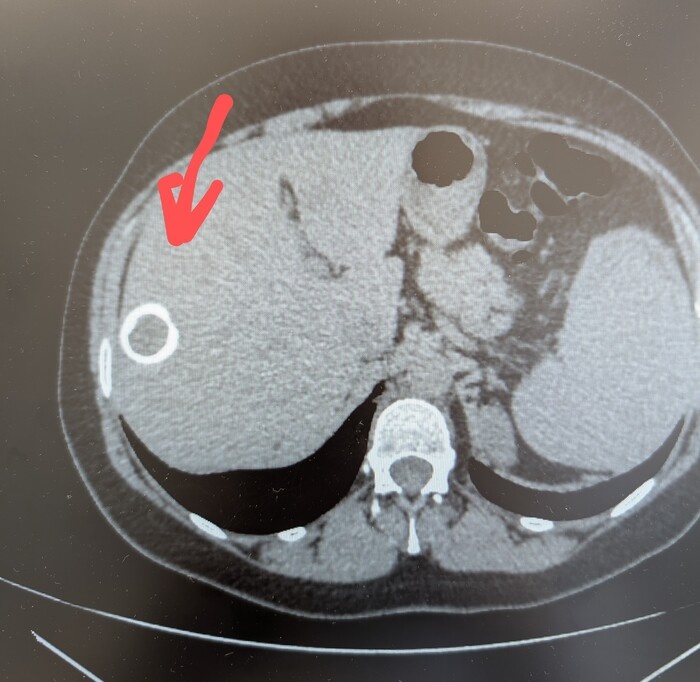

Кисты в лёгких, естественно, никуда не делись. В брюшной полости нечто (липома?), в шейке матки ещё одно нечто. А в печени вот такая красота:

Дальше, с подозрением на эхинококкоз печени, за дело взялись инфекционисты и хирурги.